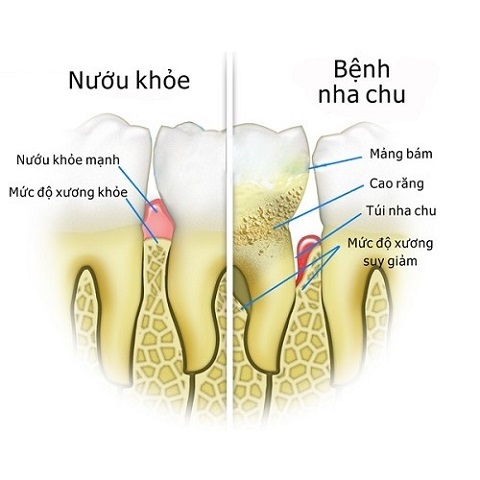

I. Nha chu và bệnh nha chu là gì?

Nha chu là tổ chức các mô xung quanh chân răng có chắc năng bảo vệ và nâng đỡ chân răng, giúp răng khỏe mạnh.

II. Bệnh nha chu là gì và tác hại của nó?

Bệnh nha chu là hiện tượng viêm nhiễm các vùng mô xung quanh chân răng. Khi nướu và các mô xung quanh chân răng bị viêm nhiễm, chúng sẽ tách ra khỏi chân răng, chân răng không còn lớp nâng đỡ và bảo vệ, ở xương chân răng cũng bị viêm nhiễm dẫn đến tiêu xương hàm. Cuối cùng là lung lay chân răng và mất răng nếu không điều trị kịp thời.